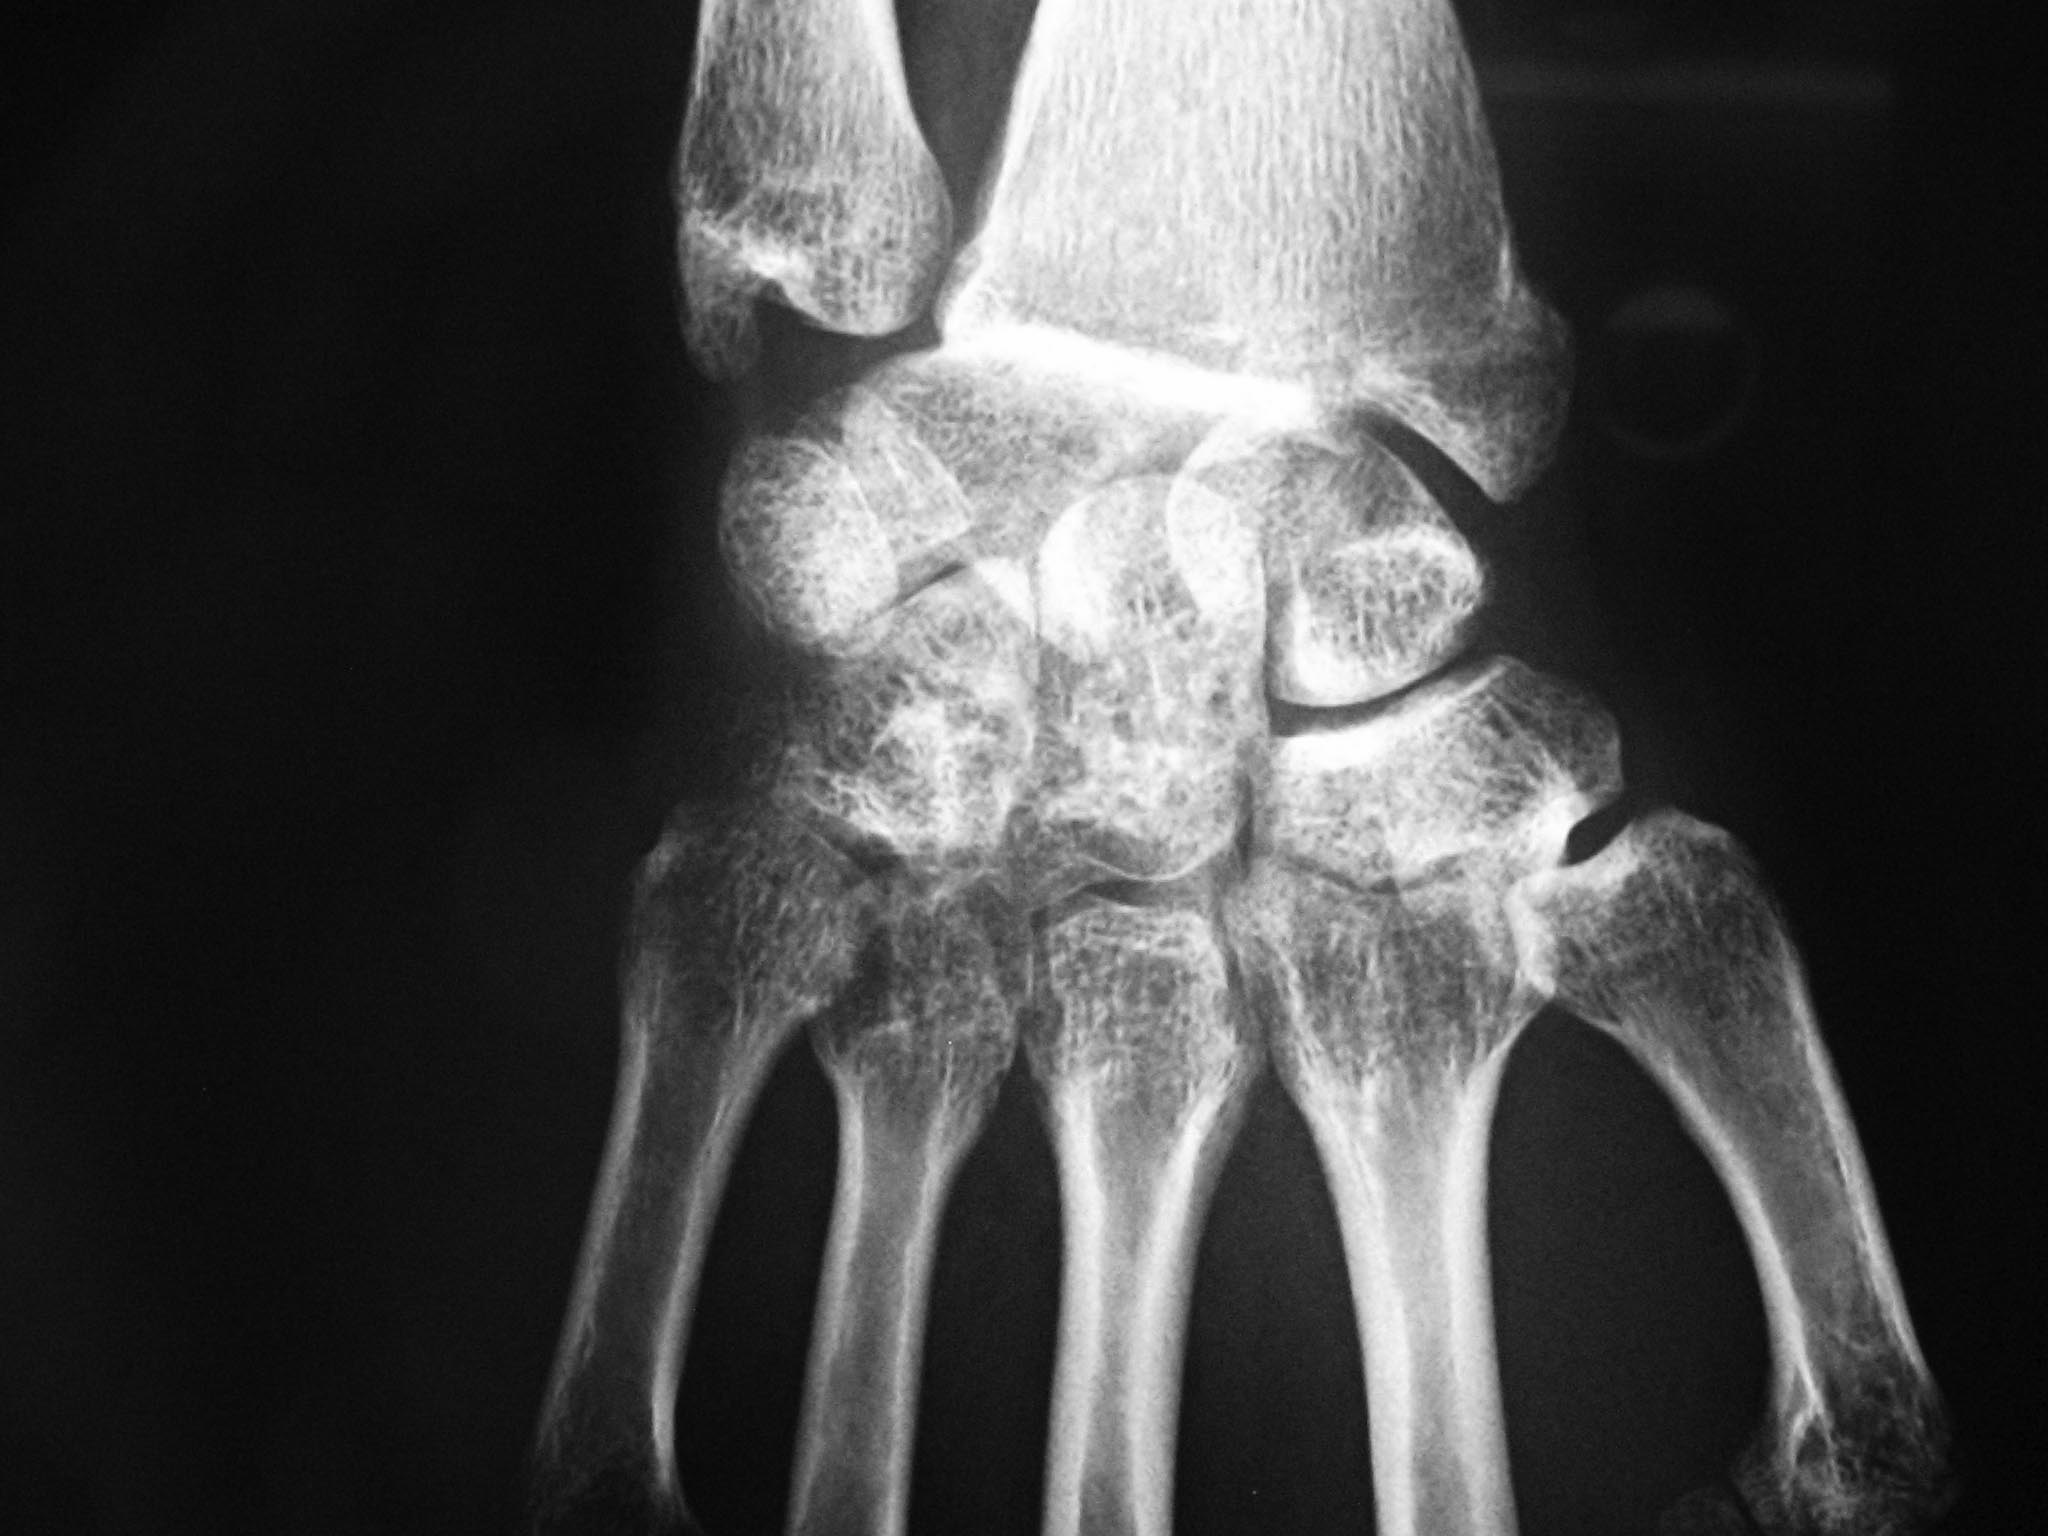

травма месячной давности, на сегодняшний день мы имеем неправильно сросшийся перелом шиловидного отростка лучевой кости, вывих полулунной кости и альгодистрофию лучезапястного сустава.

прямая проекция

Вероятнее всего, речь идет о более сложной, чем чресшиловидноперилунарный вывих кисти травме. Лечение оперативное. Чтобы оценить полный объем повреждения нужны рентгенограммы в дополнительных проекциях, а лучше всего - КТ.